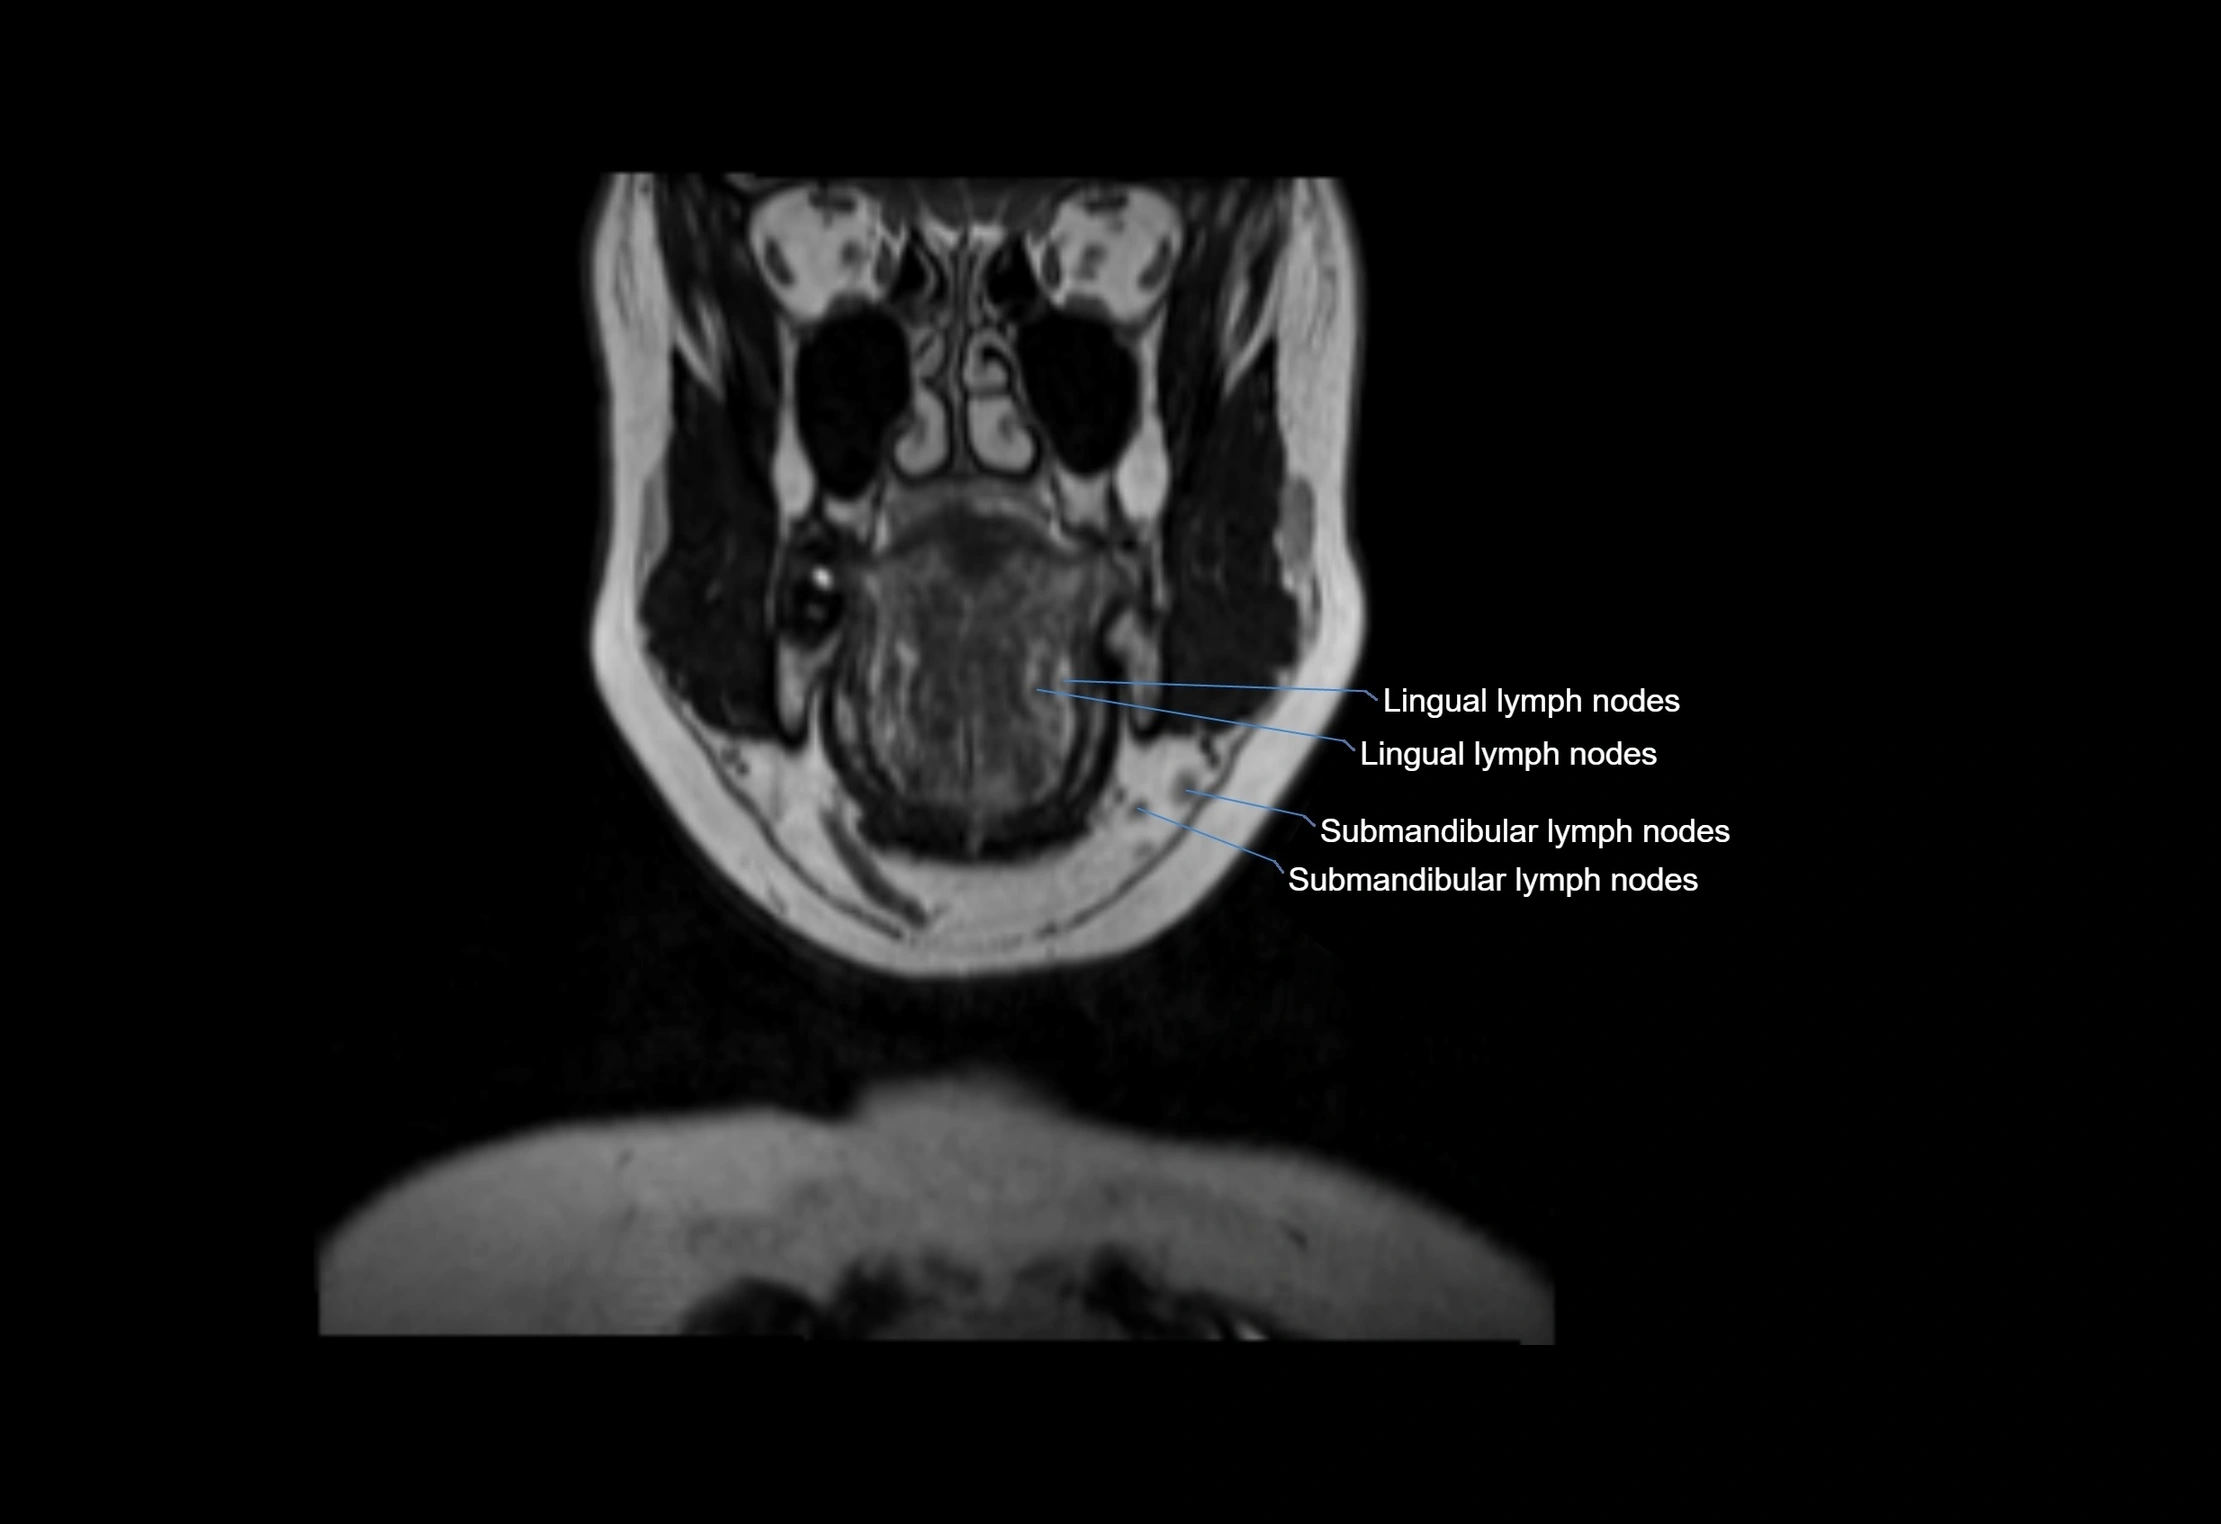

MRI images

image